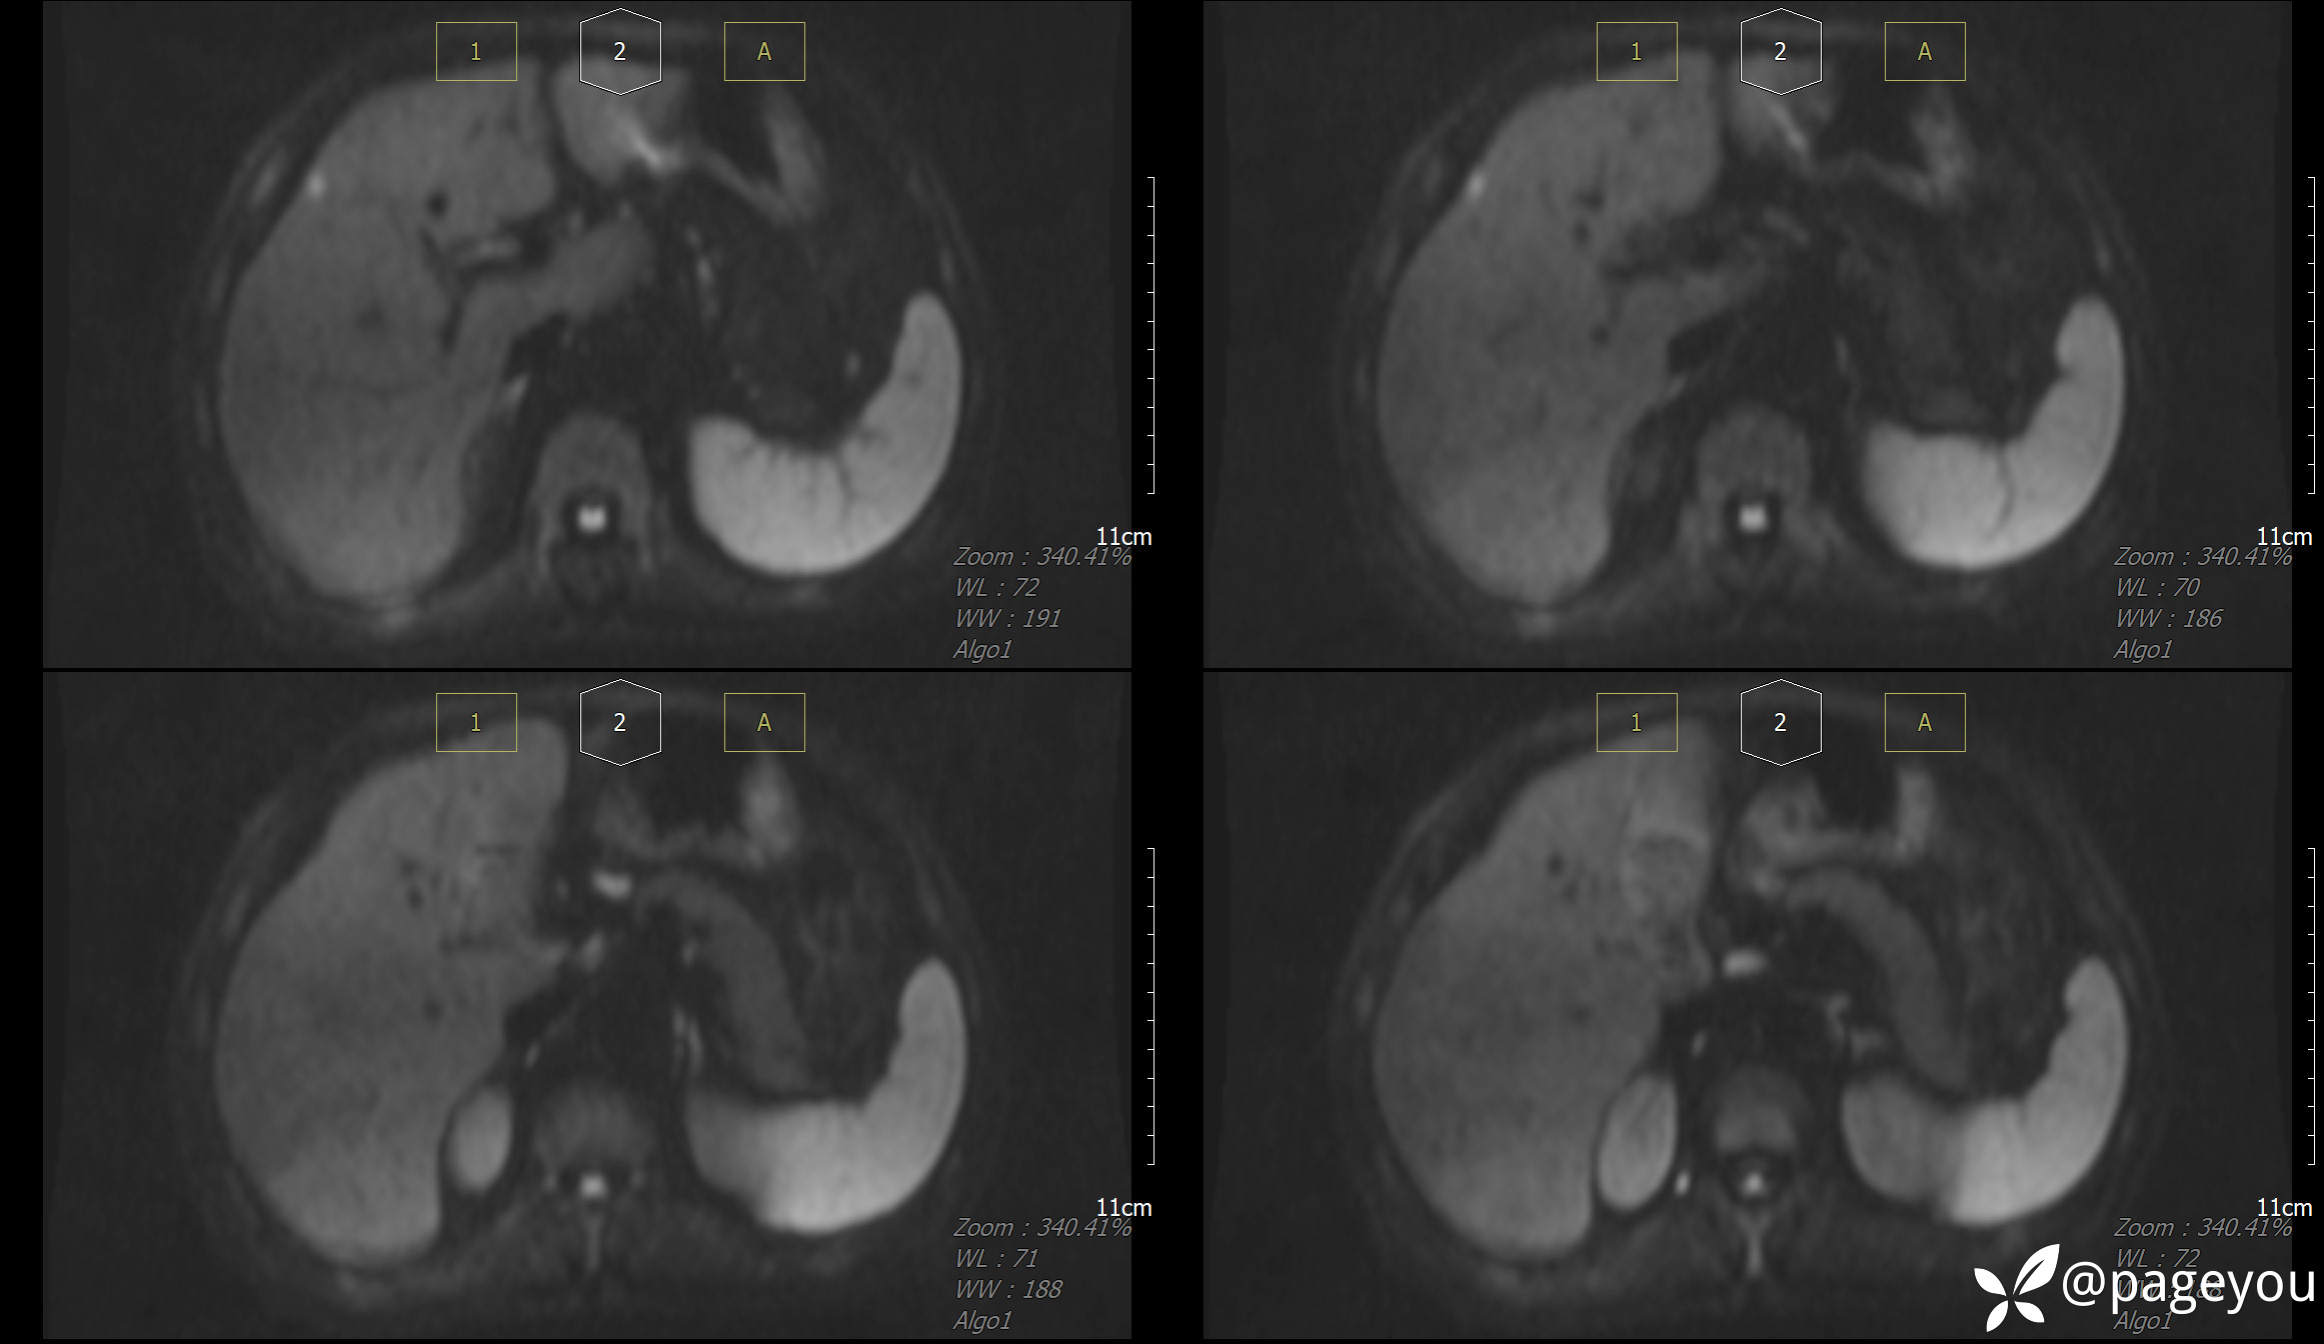

MRI检查: